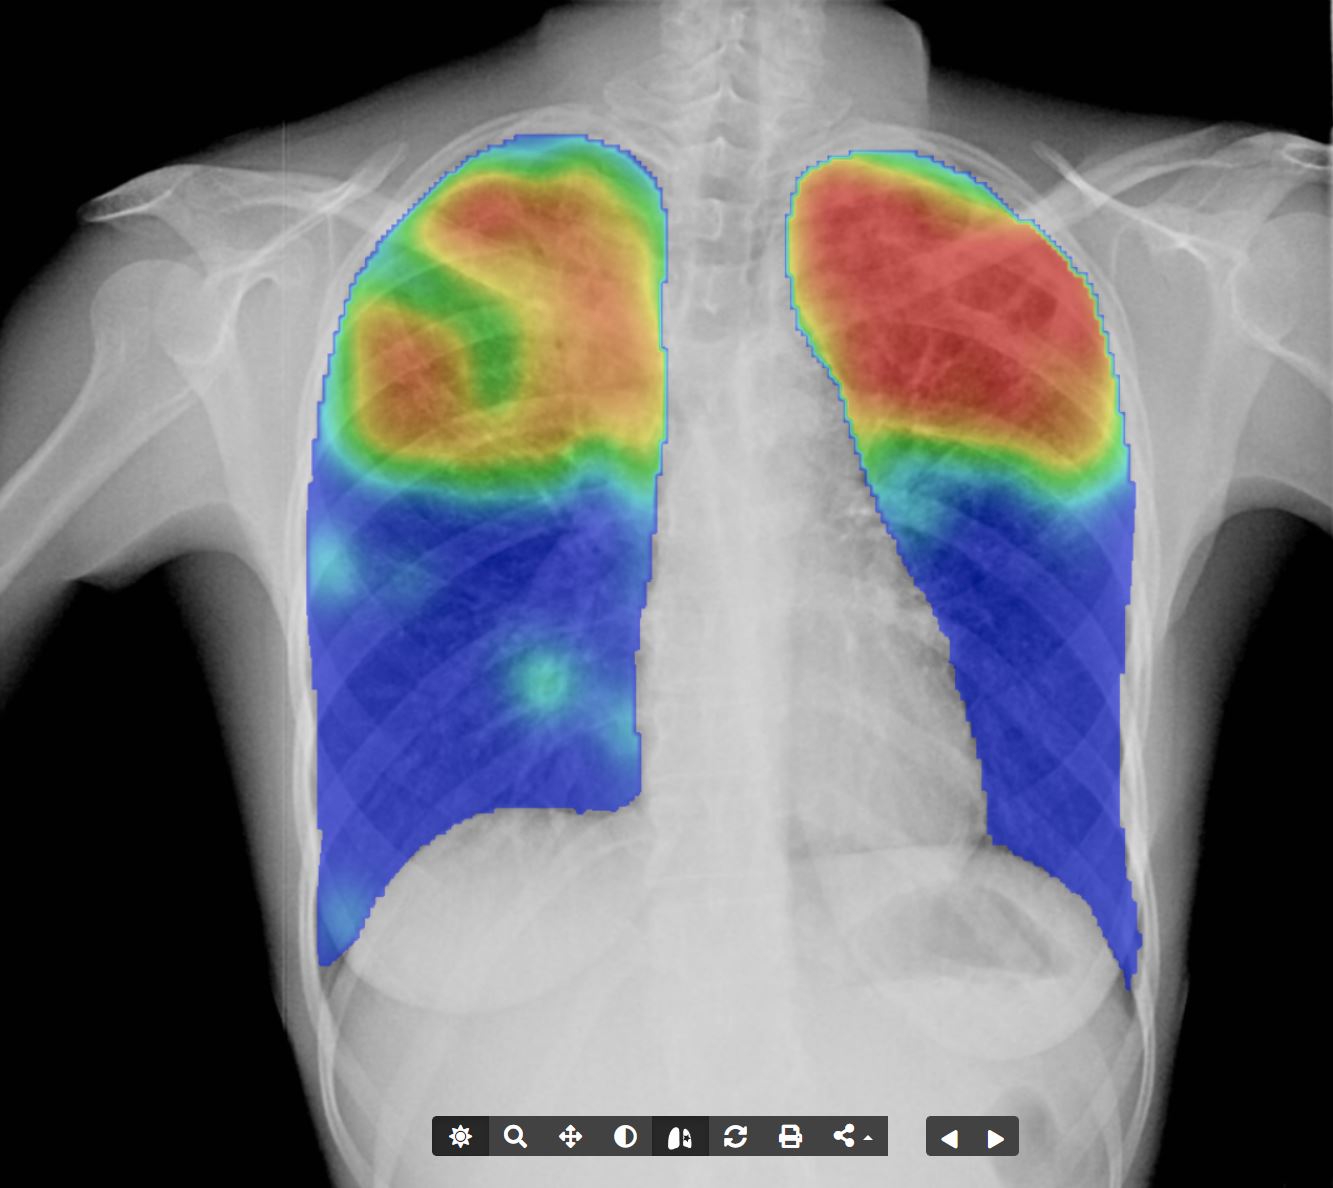

Artificial Intelligence (AI) Screening

Revolutionize diagnostic processes with AI-powered screening solutions from DataHive:

- Automated analysis for pathologies, including tuberculosis and silicosis.

- Official reseller of Delft CAD4TB and CAD4Silicosis, a WHO-endorsed CE-approved screening tool.

- Customized AI model development to meet unique needs.

- Experience CAD4TB here.